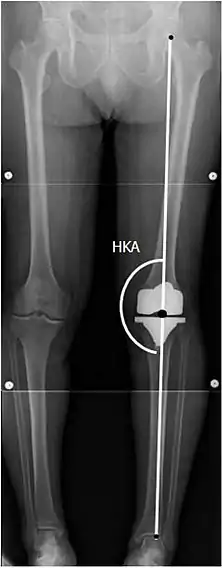

![]() |

Ángulos comúnmente medidos antes de la cirugía de reemplazo de rodilla: |

Para indicar el reemplazo de rodilla en caso de osteoartritis, su clasificación radiográfica y la gravedad de los síntomas deben ser sustanciales. Dicha radiografía debe consistir en radiografías en carga de ambas rodillas: AP, lateral y 30 grados de flexión. Es posible que las proyecciones AP y lateral no muestren un estrechamiento del espacio articular, pero la vista en flexión de 30 grados es más sensible al estrechamiento. También se utilizan proyecciones de longitud completa para ajustar la prótesis para proporcionar un ángulo neutro para la extremidad inferior distal. Dos ángulos utilizados para este propósito son:

- Ángulo cadera-rodilla-eje (CRE),[8] un ángulo formado entre una línea que pasa por el eje longitudinal de la diáfisis femoral y su eje mecánico, que es una línea desde el centro de la cabeza femoral hasta la muesca intercondilar de la diáfisis femoral. fémur.[10]

- Ángulo cadera-rodilla-tobillo (CRT),[9] que es un ángulo entre el eje mecánico femoral y el centro de la articulación del tobillo.[10] Normalmente se encuentra entre 1.0° y 1.5° de varo en adultos.[11]